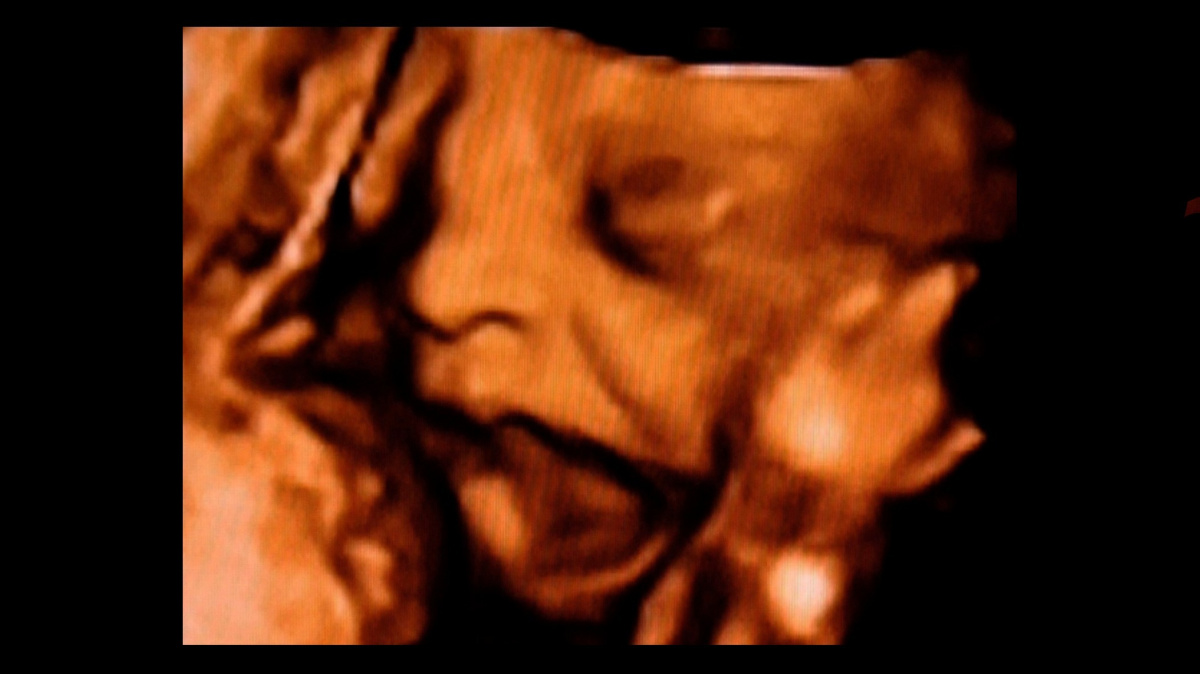

Ultrazvukový sken plodu v děloze. zdroj: Profimedia

Ultrazvukové technologie nám umožnily nahlédnout do dělohy a pozorovat plody v jejich vývoji. Například snímky publikované v časopise Archives of Disease in Childhood (Archivy dětských nemocí) v roce 2005 ukazují plod v 33. týdnu, jehož obličej nese rysy pláče.

Tým vývojové psycholožky Nadji Reisslandové z Durhamské univerzity v Anglii analyzoval vývoj mimiky v děloze sledováním pohybů plodů ve druhém a třetím trimestru pomocí 4D ultrazvukového skenování v prostorovém zobrazení a v reálném čase